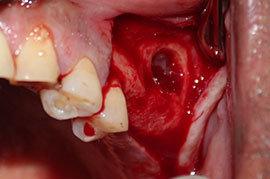

Surgery Related Complications

Incision Line Opening

Infections

Neve Damage etc

Bone Grafting Complications